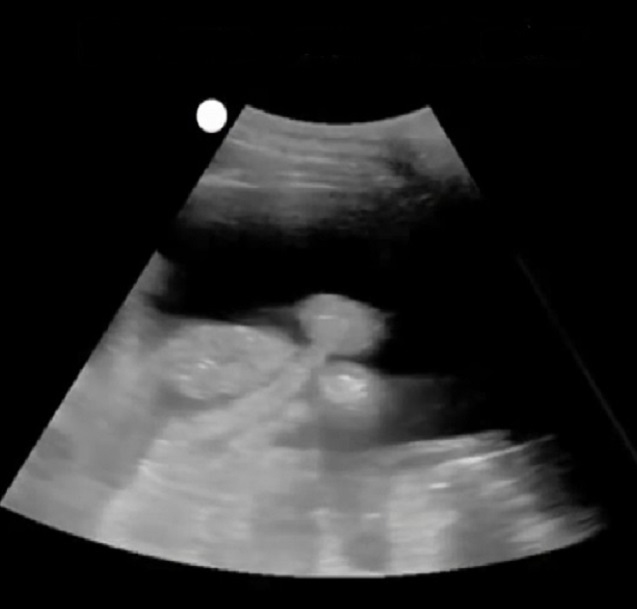

Moderate Amount of Ascites Image